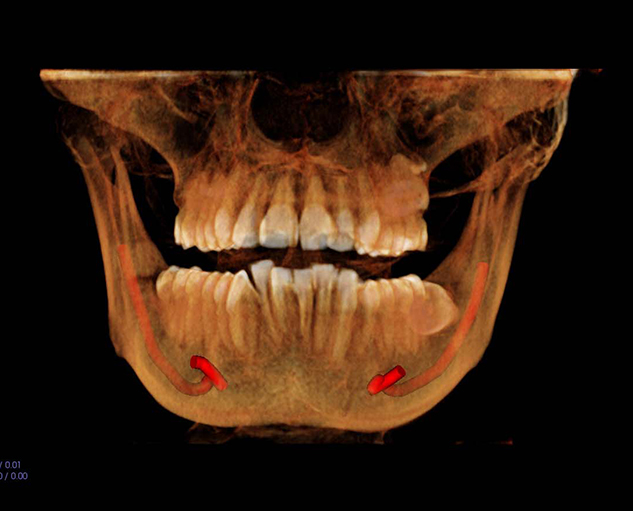

Teleradiology is an internet based radiology system wherein captured images from sources like X-Ray, CT Scan, CBCT Scan, MRI etc are sent to another location via web,so that an expert radiologist at another location can read the images for the purpose of generating reports and image portfolios.

On every case submitted, we ask you to identify the clinical purpose(s). Radreaders has developed specific diagnostic objectives for each clinical purpose that will be addressed by the radiologist. This ensures that the report is relevant to your diagnosis and treatment planning.

Click on the links below to view sample reports for some commonly indicated clinical purposes:

Implant

Pathology

TMD

Orthodontics

Third Molar

Endo

Cephalometric